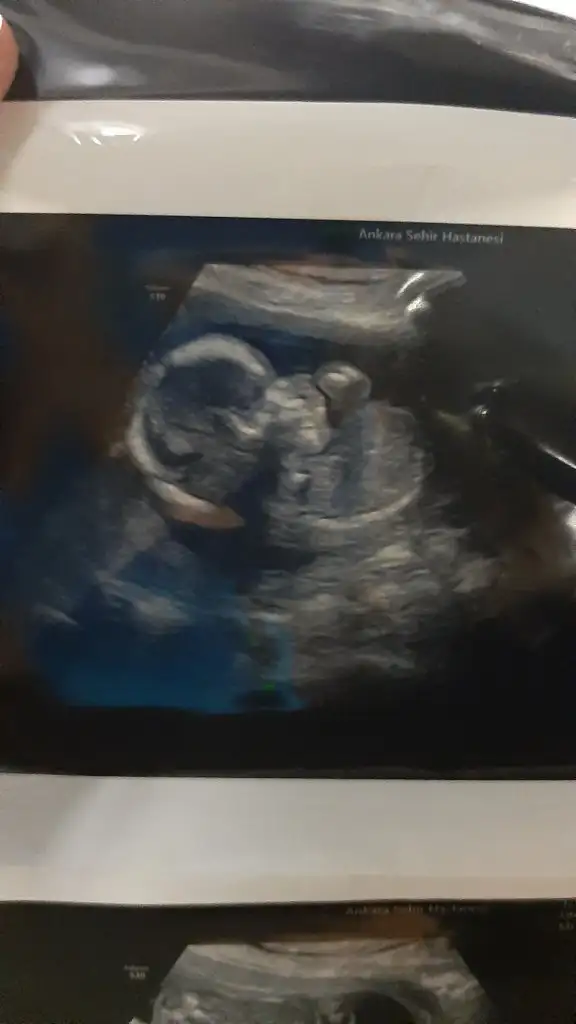

Hiç görünmüyor kimin bebeği

Yüzü görünüyor prensesinBenim teyzesi busefer okadar net fotoları verdi

❤❤❤❤❤❤❤❤❤❤❤Yüzü görünüyor prensesinmasallah